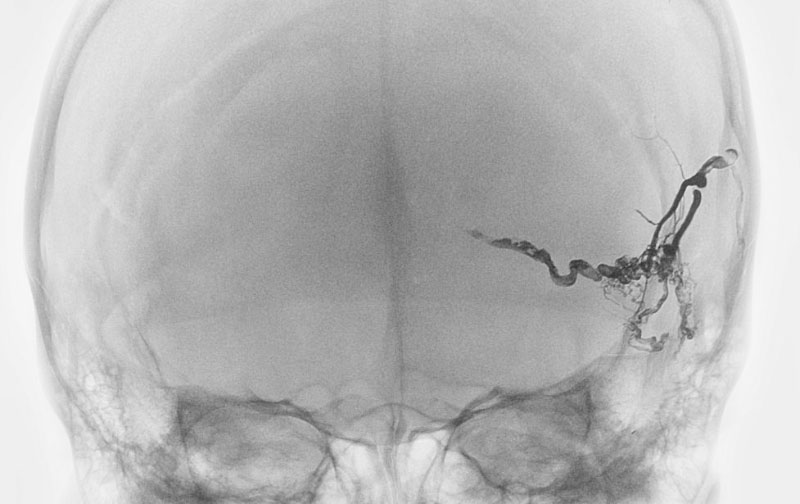

1586

'25年10月6日

硬膜動静脈瘻

40代

大阪府の病院

中

治療